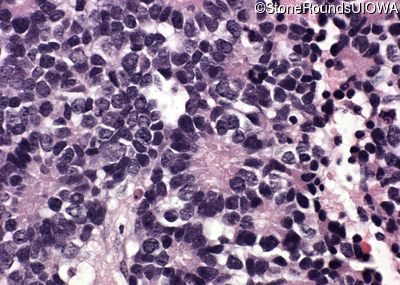

Pathology - Left - -

Exemplar